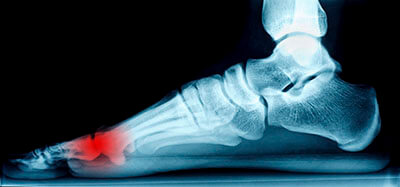

Morton’s neuroma may develop when the tissue around one of the nerves leading to your foot begins to thicken. When this occurs, you may experience some discomfort as if you were standing on a pebble stuck in your shoe. Most symptoms will not appear outwardly and will be experienced in the form of a sharp, burning pain in the ball of the foot, as well as a stinging or burning feeling in the toes that may sometimes lead to numbness.

Symptoms of Morton’s neuroma include tingling, burning, numbness, pain, and the feeling that either something is inside the ball of the foot or that something in one’s shoe or sock is bunched up. Symptoms typically begin gradually and can even go away temporarily by removing one’s shoes or massaging the foot. An increase in the intensity of symptoms correlates with the increasing growth of the neuroma.